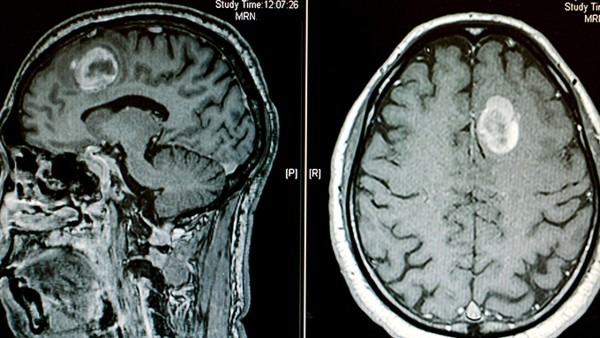

脑胶质瘤的病理分型

脑胶质瘤是一种常见的脑部肿瘤,起源于脑组织中的胶质细胞,可分为多种类型和分级。病理分型是对脑胶质瘤进行分类和描述的方法,能够指导医生选择最合适的治疗方案,预测患者的预后。在临床上,常见的脑胶质瘤病理分型包括星形细胞瘤、少突胶质细胞瘤、弥漫性星形细胞瘤等。 一、星形细胞瘤(Astrocytoma)是最常见的脑胶质瘤之一,起源于星形胶质细胞。它通常根据组织学特征和细胞恶性程度分为四级:Ⅰ级为星形细胞瘤、Ⅱ级为低级星形细胞瘤、Ⅲ级为恶性星形细胞瘤、Ⅳ级为胶质母细胞瘤(Glioblastoma multiforme,GBM),是最为恶性和侵袭性的类型之一。星形细胞瘤的治疗一般包括手术切除、放疗和化疗等方法。 二、少突胶质细胞瘤(Oligodendroglioma)起源于少突胶质细胞,通常生长较慢,分为低级和高级两种类型。少突胶质细胞瘤的治疗策略主要包括手术切除和放疗。 三、弥漫性星形细胞瘤(Diffuse Astrocytoma)是一种低级别的星形细胞瘤,通常具有较慢的生长速度,但也可能逐渐进展为更高级别的胶质瘤。治疗方法与其他星形细胞瘤类似。 综上所述,脑胶质瘤的病理分型对于患者的诊断、治疗和预后具有重要意义。随着医学科技的不断发展,针对不同类型的脑胶质瘤,医生们不断探索更有效的治疗策略,希望能为患者提供更好的治疗效果,并改善患者的生存质量。对于患有脑胶质瘤的患者来说,及时进行病理诊断和明确病理分型,对于制定个性化的治疗方案至关重要,有助于提高治疗效果,延长生存时间。